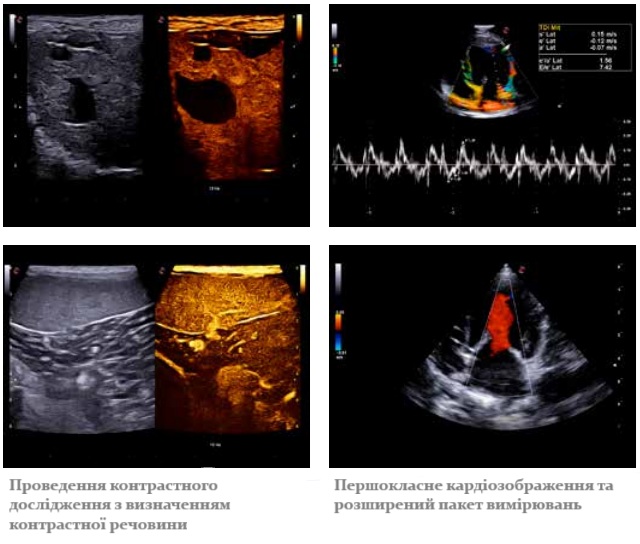

Приклади діагностичних зображень, отриманих на УЗД сканері MyLab X75 VET: проведення контрастного дослідження органів черевної порожнини та розширений пакет кардіологічних вимірювань з доплером